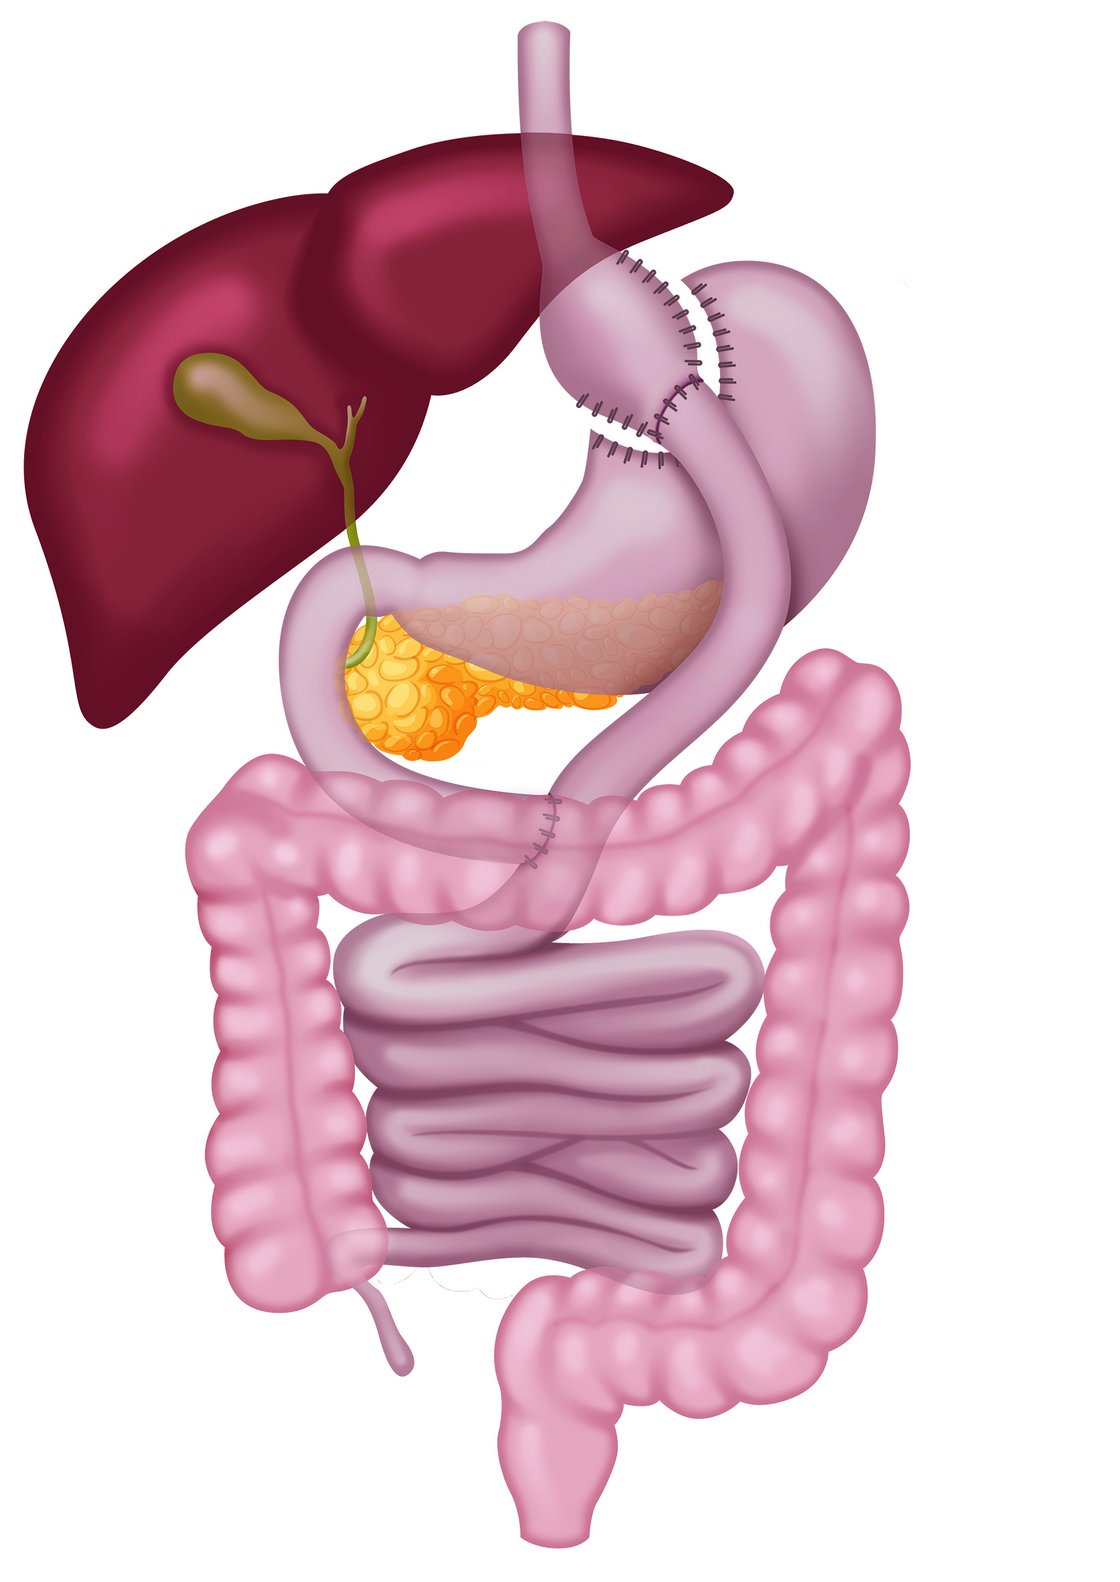

- BMI unter 50 kg /m²

- Verkleinerung des Magens (Magenpouch) und Umstellung der Nahrungspassage mit zwei Nahtverbindungen (Anastomosen)

- zusätzliche Aufnahme von Vitaminen und Spurenelementen notwendig